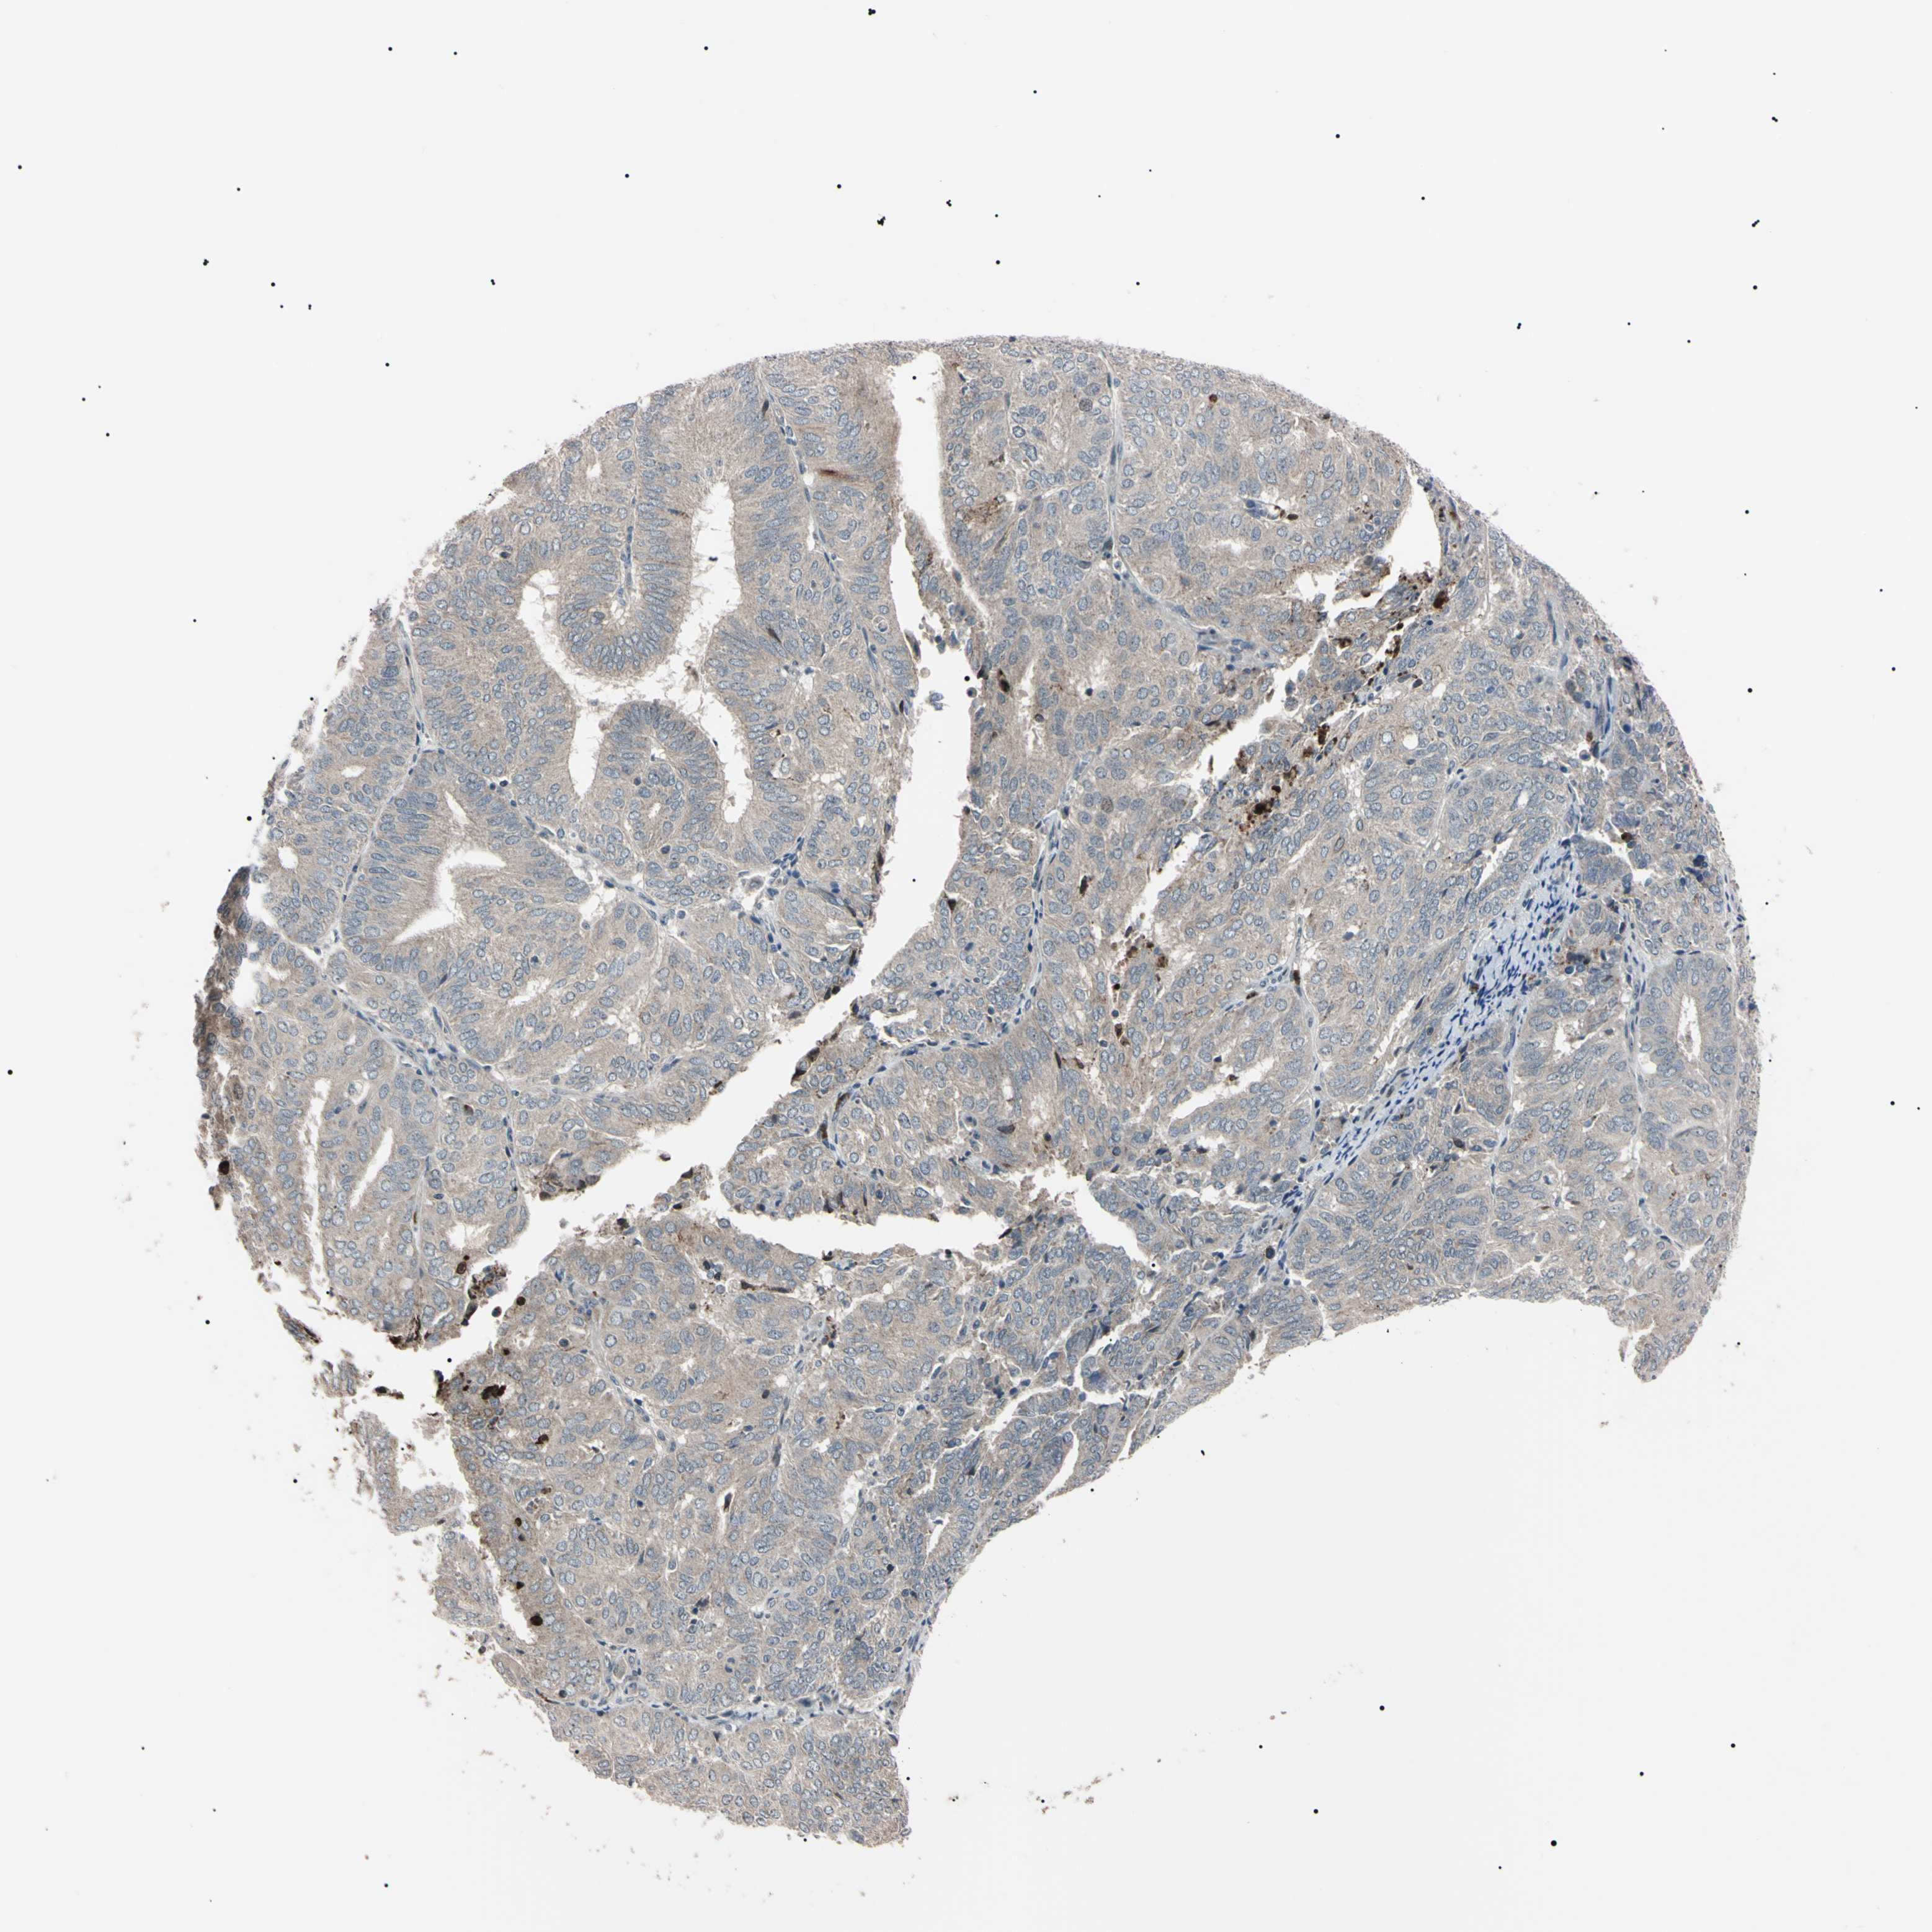

ENDOMETRIAL CANCER - Protein expressioni

A mouse-over function shows sample information and annotation data. Click on an image to view it in a full screen mode. Samples can be filtered based on level of antibody staining by selecting one or several of the following categories: high, medium, low and not detected. The assay and annotation is described here.

Note that samples used for immunohistochemistry by the Human Protein Atlas do not correspond to samples in the TCGA dataset.

Antibody stainingi

Antibody staining in the annotated cell types in the current human tissue is reported as not detected, low, medium, or high, based on conventional immunohistochemistry profiling in selected tissues. This score is based on the combination of the staining intensity and fraction of stained cells.

Each image is clickable and will lead to virtual microscopy that enables deeper exploration of all samples and also displays staining intensity scores, fraction scores and subcellular localization as well as patient and tissue information for each sample.

Antibody HPA008052

Antibody CAB010277

Staining

High

Medium

Low

Not detected

Intensity

Strong

Moderate

Weak

Negative

Quantity

>75%

75%-25%

<25%

None

Location

Nuclear

Cytoplasmic/membranous

Cytoplasmic/membranous,nuclear

Adenocarcinoma, NOS